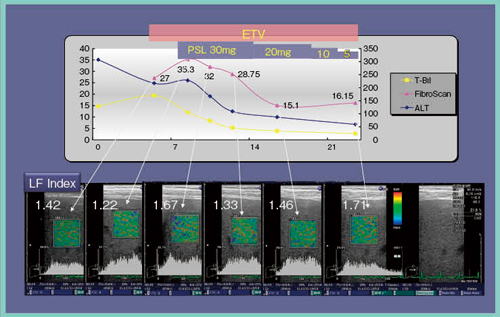

●症例2:慢性B型肝炎再燃(図4)

再燃が発見された時点では,ALT 200〜300U/L,ビルビリン 20mg/dl前後と高かったが,エンテカビル(ETV)とプレドニゾロンの併用により,ALTが漸減した。経過中,FibroScanは27,35.3kPaと非常に高い数値を保っていたが,治療により漸減し,15kPa前後をキープするに至った。この間,RTEは1.42から1.6,1.7程度のLF Index値であり,線維化は組織学的にはF2ないしF3であった。この症例でも,FibroScanは高すぎる数値を出してしまい,線維化を正確にとらえられなかった。

図4 症例2:慢性B型肝炎再燃